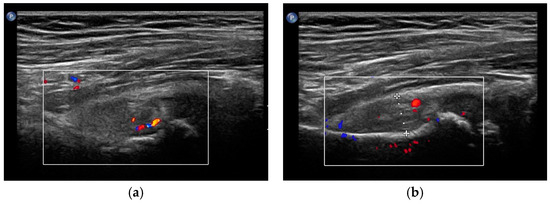

- Maruszczak, K.; Kochman, M.; Madej, T.; Gawda, P. Ultrasound Imaging in Diagnosis and Management of Lower Limb Injuries: A Comprehensive Review. Med. Sci. Monit. 2024, 30, e945413. [Google Scholar] [CrossRef] [PubMed]

- Czyrny, Z. Osgood-Schlatter disease in ultrasound diagnostics—A pictorial essay. Med. Ultrason. 2010, 12, 323–335. [Google Scholar] [PubMed]